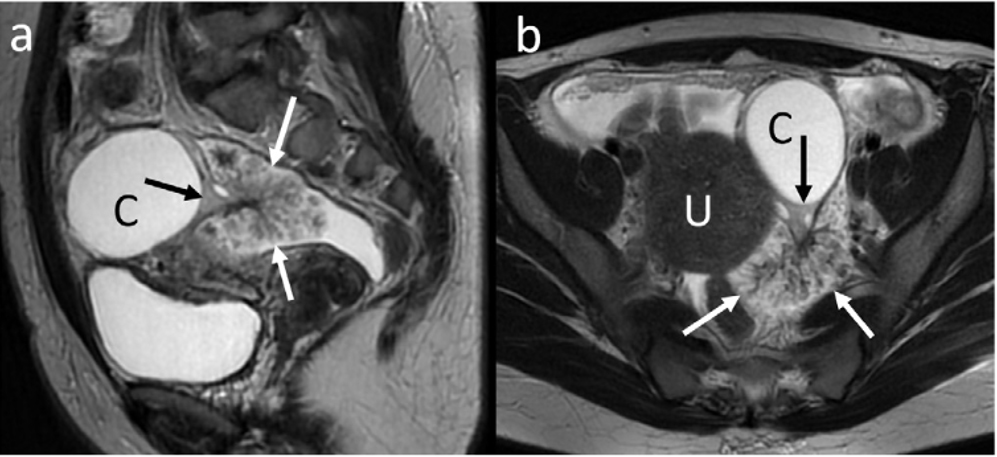

MRI:

両側卵巣に嚢胞構造(T2WI高信号、T1WI軽度低信号)

骨盤底部、右付属器表面に付着する腫瘤

明瞭なT2WI高信号、T1WI低信号、DWI高信号、ADC高値

右卵巣表面に連なるT2WI低信号の樹枝状構造

樹枝状構造は造影され、腫瘤本体は造影効果が弱い

少量の腹水と軽度腹膜肥厚